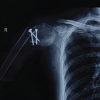

Informed consent was obtained from all participants. Demographic details and relevant medical history were collected using a structured proforma. Clinical examination and surgical intervention were carried out using standard procedures at the SBMCH. [Fig. 1] [Fig. 2] [Fig. 3] Postoperative evaluation for implant loosening was done through serial radiographs, specifically assessing for radiolucency at the bone-cement interface. Functional outcomes were assessed 26 using the CONSTANT-Murley score and UCLA shoulder score. All data were entered in Microsoft Word and analyzed using SPSS software version 24. [Fig. 4].

Figure 1: Pre-operation X-ray.